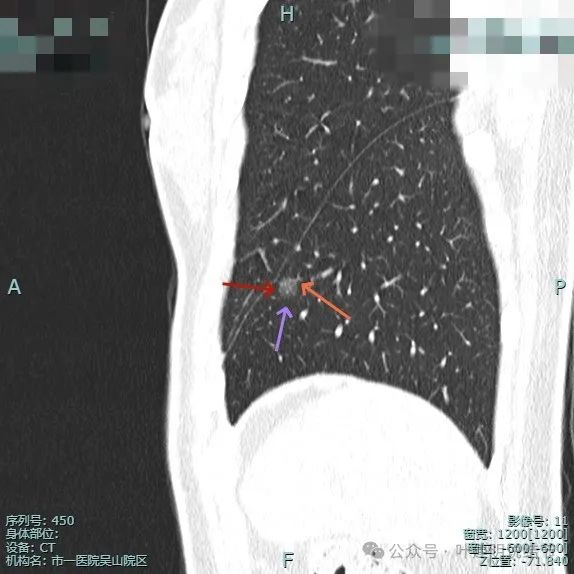

靶重建图像:

病灶边缘毛糙,微小血管进入明显。灶内密度略不均。

血管进入与穿行明显,而且在病灶内有发出血管分支,病灶表面不平,有毛刺征。

小血管进入明显,边缘有毛刺征,整体轮廓与边界清。

血管进入,灶内小空泡征,邻近细支气管有扩张,表面有细毛刺。

多处血管征,表面毛糙,轮廓清楚,有不太典型的血管弯征,灶内密度稍不均。

叶间胸膜牵拉较平扫上明显,血管进入也明显,整体轮廓清。

灶内有点状偏高密度成分,内部密度稍显杂乱;叶间胸腊牵拉,整体轮廓清。

多支血管进入,而且灶内的血管显得较病灶外略粗与略模糊,叶间胸膜牵拉是有的,力量不强。